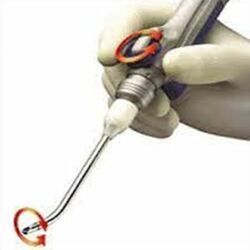

Endoscopic debrider

A sizeable number of patients of lung cancer may develop obstruction of the central airways besides it is being increasingly diagnosed in cases effected with benign disorders such as post intubation tracheal stenosis and connective tissue diseases. This necessitates an Endoscopic palliation to relieve symptoms of dyspnea, establish a diagnosis, and facilitates other therapies such as surgical resection and reconstruction. The microdebrider is one of the tools for used here.

The microdebrider comprises of three components.

- The disposable blade is a hollow metal tube coupled to suction that cuts obstructing tissue and simultaneously removes it from the airway.

- Second, the hand piece drives the blade via an electrically powered motor and is compatible with blades of various sizes and configurations. Regular wall suction tubing connects to the hand piece to provide suction to the blade.

- The console controls the hand piece via a foot pedal and allows the operator to select the speed and the direction of rotation of the blade.